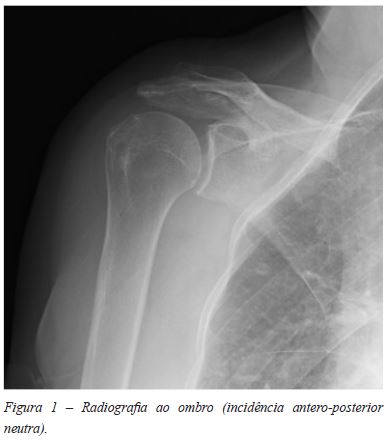

Mulher de 74 anos, antecedentes pessoais irrelevantes. Enviada à consulta de Ortopedia por omalgia direita com um ano de evolução, sem história de trauma. Ao exame objectivo apresentava dor com a mobilização articular e limitação marcada do arco de movimento, sem massas palpáveis ou sinais inflamatórios. Não apresentava déficies neurológicos. O RX do ombro foi normal (Figuras 1 e 2).